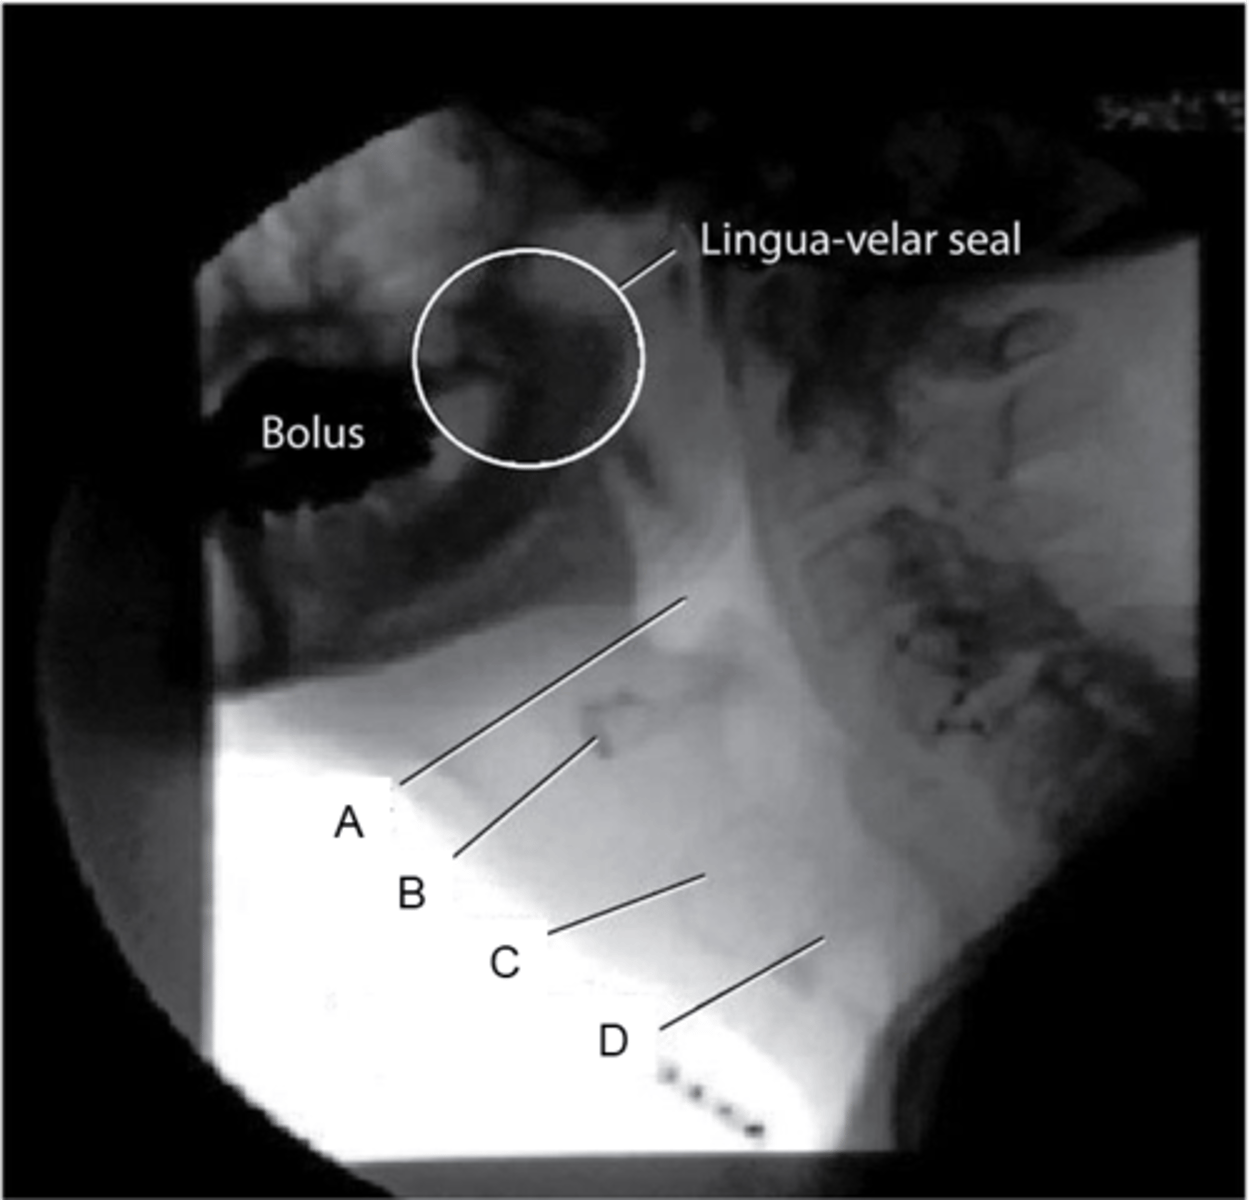

Indicate the pharynx and the hyoid bone.

A,B

Aspiration happens when a bolus passes through

D